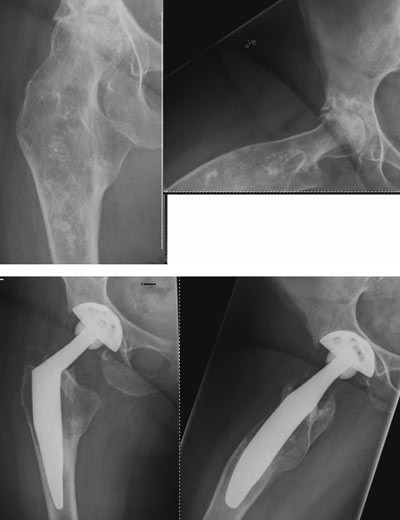

Harris’ hofteskår ble målt preoperativt og postoperativt etter ett år. Gjennomsnittlig skår preoperativt var 49 (spredning 27 – 66) og postoperativt 97 (spredning 76 – 100). Preoperativt var det aktuelle bein kortere (1 – 3 cm) hos 20 pasienter. Postoperativt var beina like lange hos 35 pasienter, hos én pasient var beinet fortsatt 1 cm for kort, og hos én pasient var beinet blitt 1 cm for langt (overkorreksjon). Eksempler på bruk av den individtilpassede hofteprotesen fremgår av figur 6, figur 7 og e-figur 8.

Den preoperative diagnosen var hoftedysplasi i 30 hofter (70 %), Calvé-Legg-Perthes’ sykdom i fem hofter, primær artrose i fire hofter og fraktursekvele i fire hofter. Graden av hoftedysplasi ble vurdert etter Crowes inndeling (18). 25 hofter hadde dysplasi grad 1 (mild), og fem hofter dysplasi grad 2 (lav dislokasjon). Pasienter med høy dislokasjon ble ikke operert i Arendal, men rutinemessig henvist til Ortopedisk avdeling, Rikshospitalet, der man har lang erfaring med slike nedhentingsoperasjoner (19). Seks av hoftene var tidligere operert med takplastikk, seks var operert med femurosteotomi og fire hofter var tidligere operert for brudd.

Operasjonen ble gjennomført som planlagt hos alle pasientene uten behov for konvertering til en sementert femurkomponent ved noen av inngrepene. Operasjonstiden var 75 – 140 minutter, snitt 96 minutter. Den preoperative dokumentasjonen var presis, og collumkuttet var innenfor 3 mm av planlagt nivå hos alle pasientene.